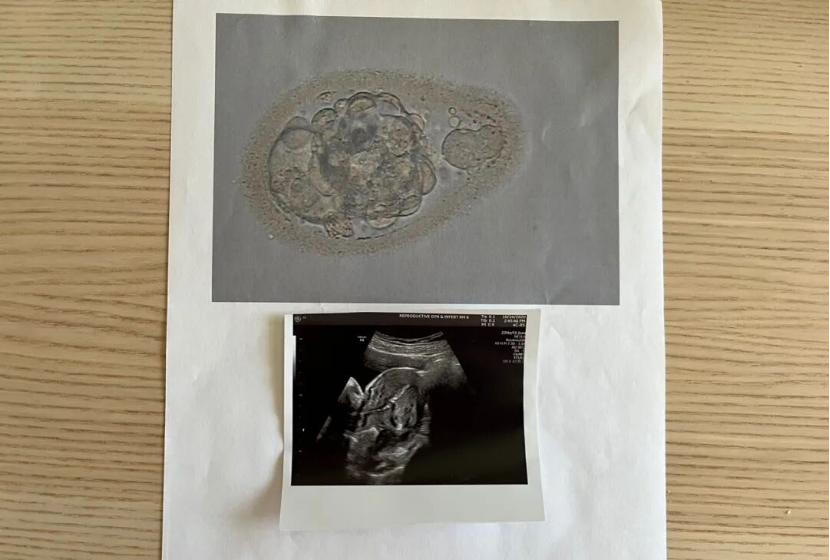

3 月 18 日是移植日,早上洗澡后按要求慢慢喝够 2L 水憋尿。11:35 抵达诊所,和老公一起换好衣服等候,护士先出示了解冻后的囊胚照片,确认信息后让我们签字。12:20 进入手术室,护士通过 B 超发现我膀胱太满,让我适量排尿,这可真是个技术活 —— 憋尿难,控制排尿更难!

5 月 27 日是第二次移植日,受疫情影响,老公不能陪同进入诊所,只能在停车场等我。移植过程依然很快,但没有了老公的陪伴,我格外紧张。护士同样给了囊胚照片和移植 B 超图,可还是没告知囊胚等级,这让我心里隐隐有些不安。

10 月 14 日,第三次移植日,依然是我独自前往诊所。护士说这颗囊胚虽然不是圆形,但合格,我看着囊胚照片,心里充满了期待。术后每天按时吃药、打黄体酮油针,老公的打针技术已经非常熟练了 —— 打针前先把药瓶捂热,我用冰袋敷一下屁股,打完后再热敷或走动,疼痛感减轻了很多。